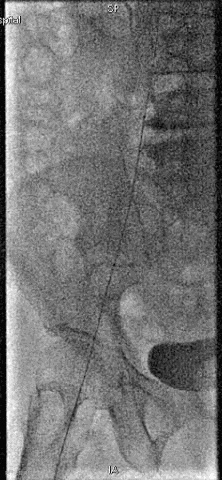

手术过程

抽吸结果